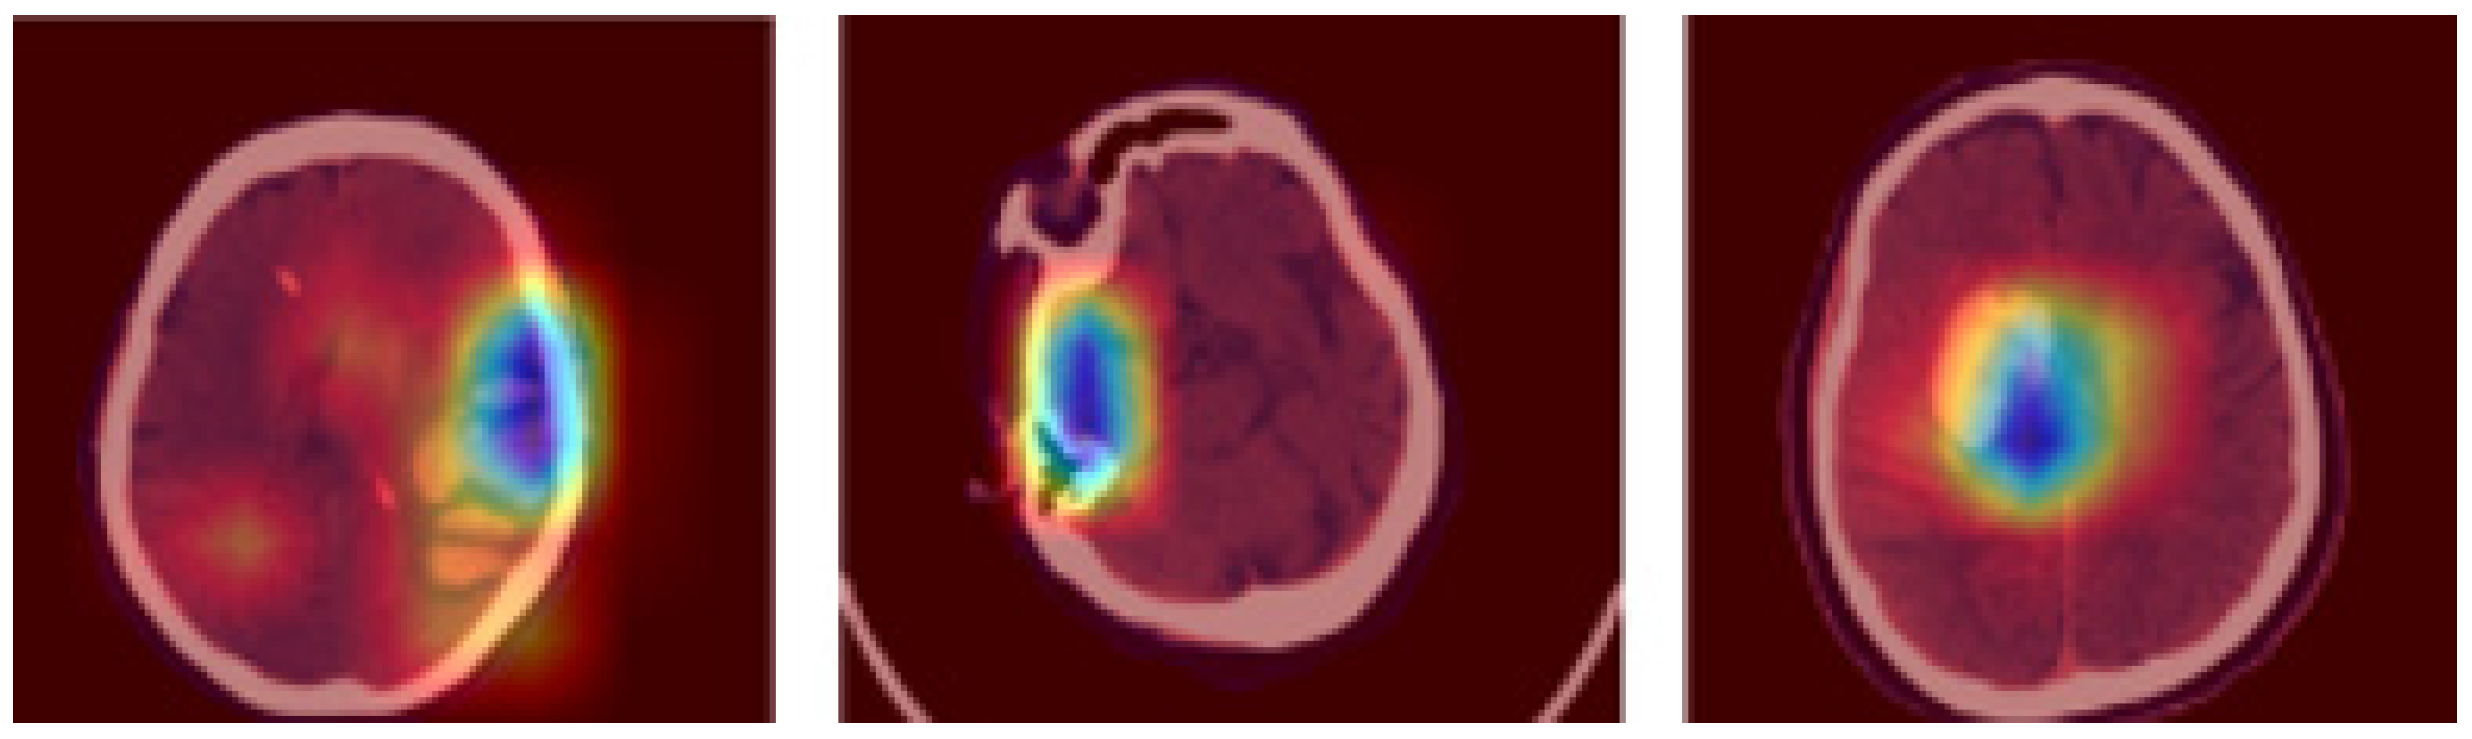

where and indicates the degree of membership of the iterations and , and specifies the highest vector value. Furthermore, the hybrid feature extraction is accomplished using HoG, LBP, and LTP descriptors for extracting features from the segmented images. The sample segmented 3D brain scans are depicted in Figure 3.

Figure 3.

Sample segmented 3D brain scans.